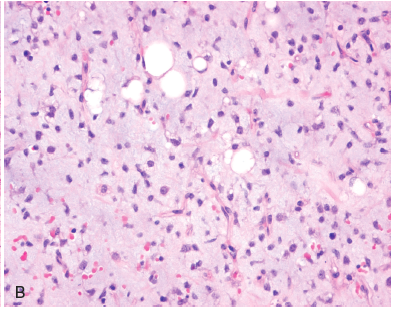

What is the morphology of the myxoid type of liposarcoma?

Basophilic myxoid matrix, arborizing capillaries (“chicken-wire”) + primitive cells at various stages of adipocyte differentiation